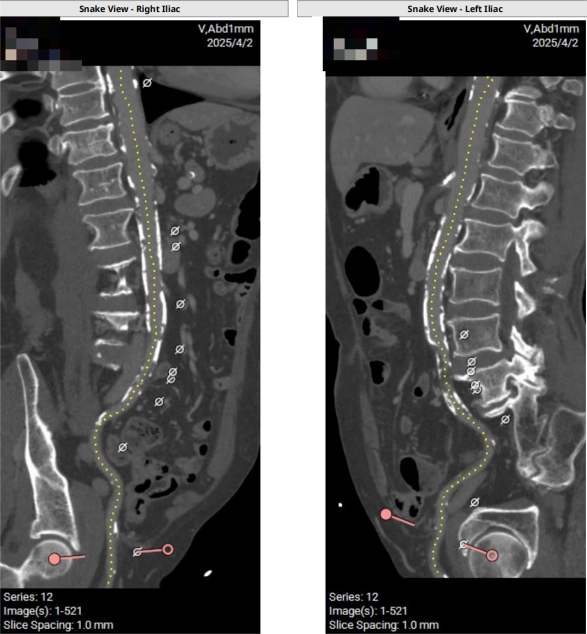

术前CT评估示

三叶瓣主动脉瓣,瓣环面积面积491.0mm²,瓣环面积折算直径为25.0mm,LVOT平均直径为24.2mm。主动脉窦部(LC/RC/NC)直径:28.8mm,26.5mm,29.6mm,STJ均径27.3mm。

冠脉高度可,冠脉闭塞低风险。

中度钙化

外周血管入路评估示:外周入路弥漫性闭塞,锁骨下动脉内径细小并钙化。